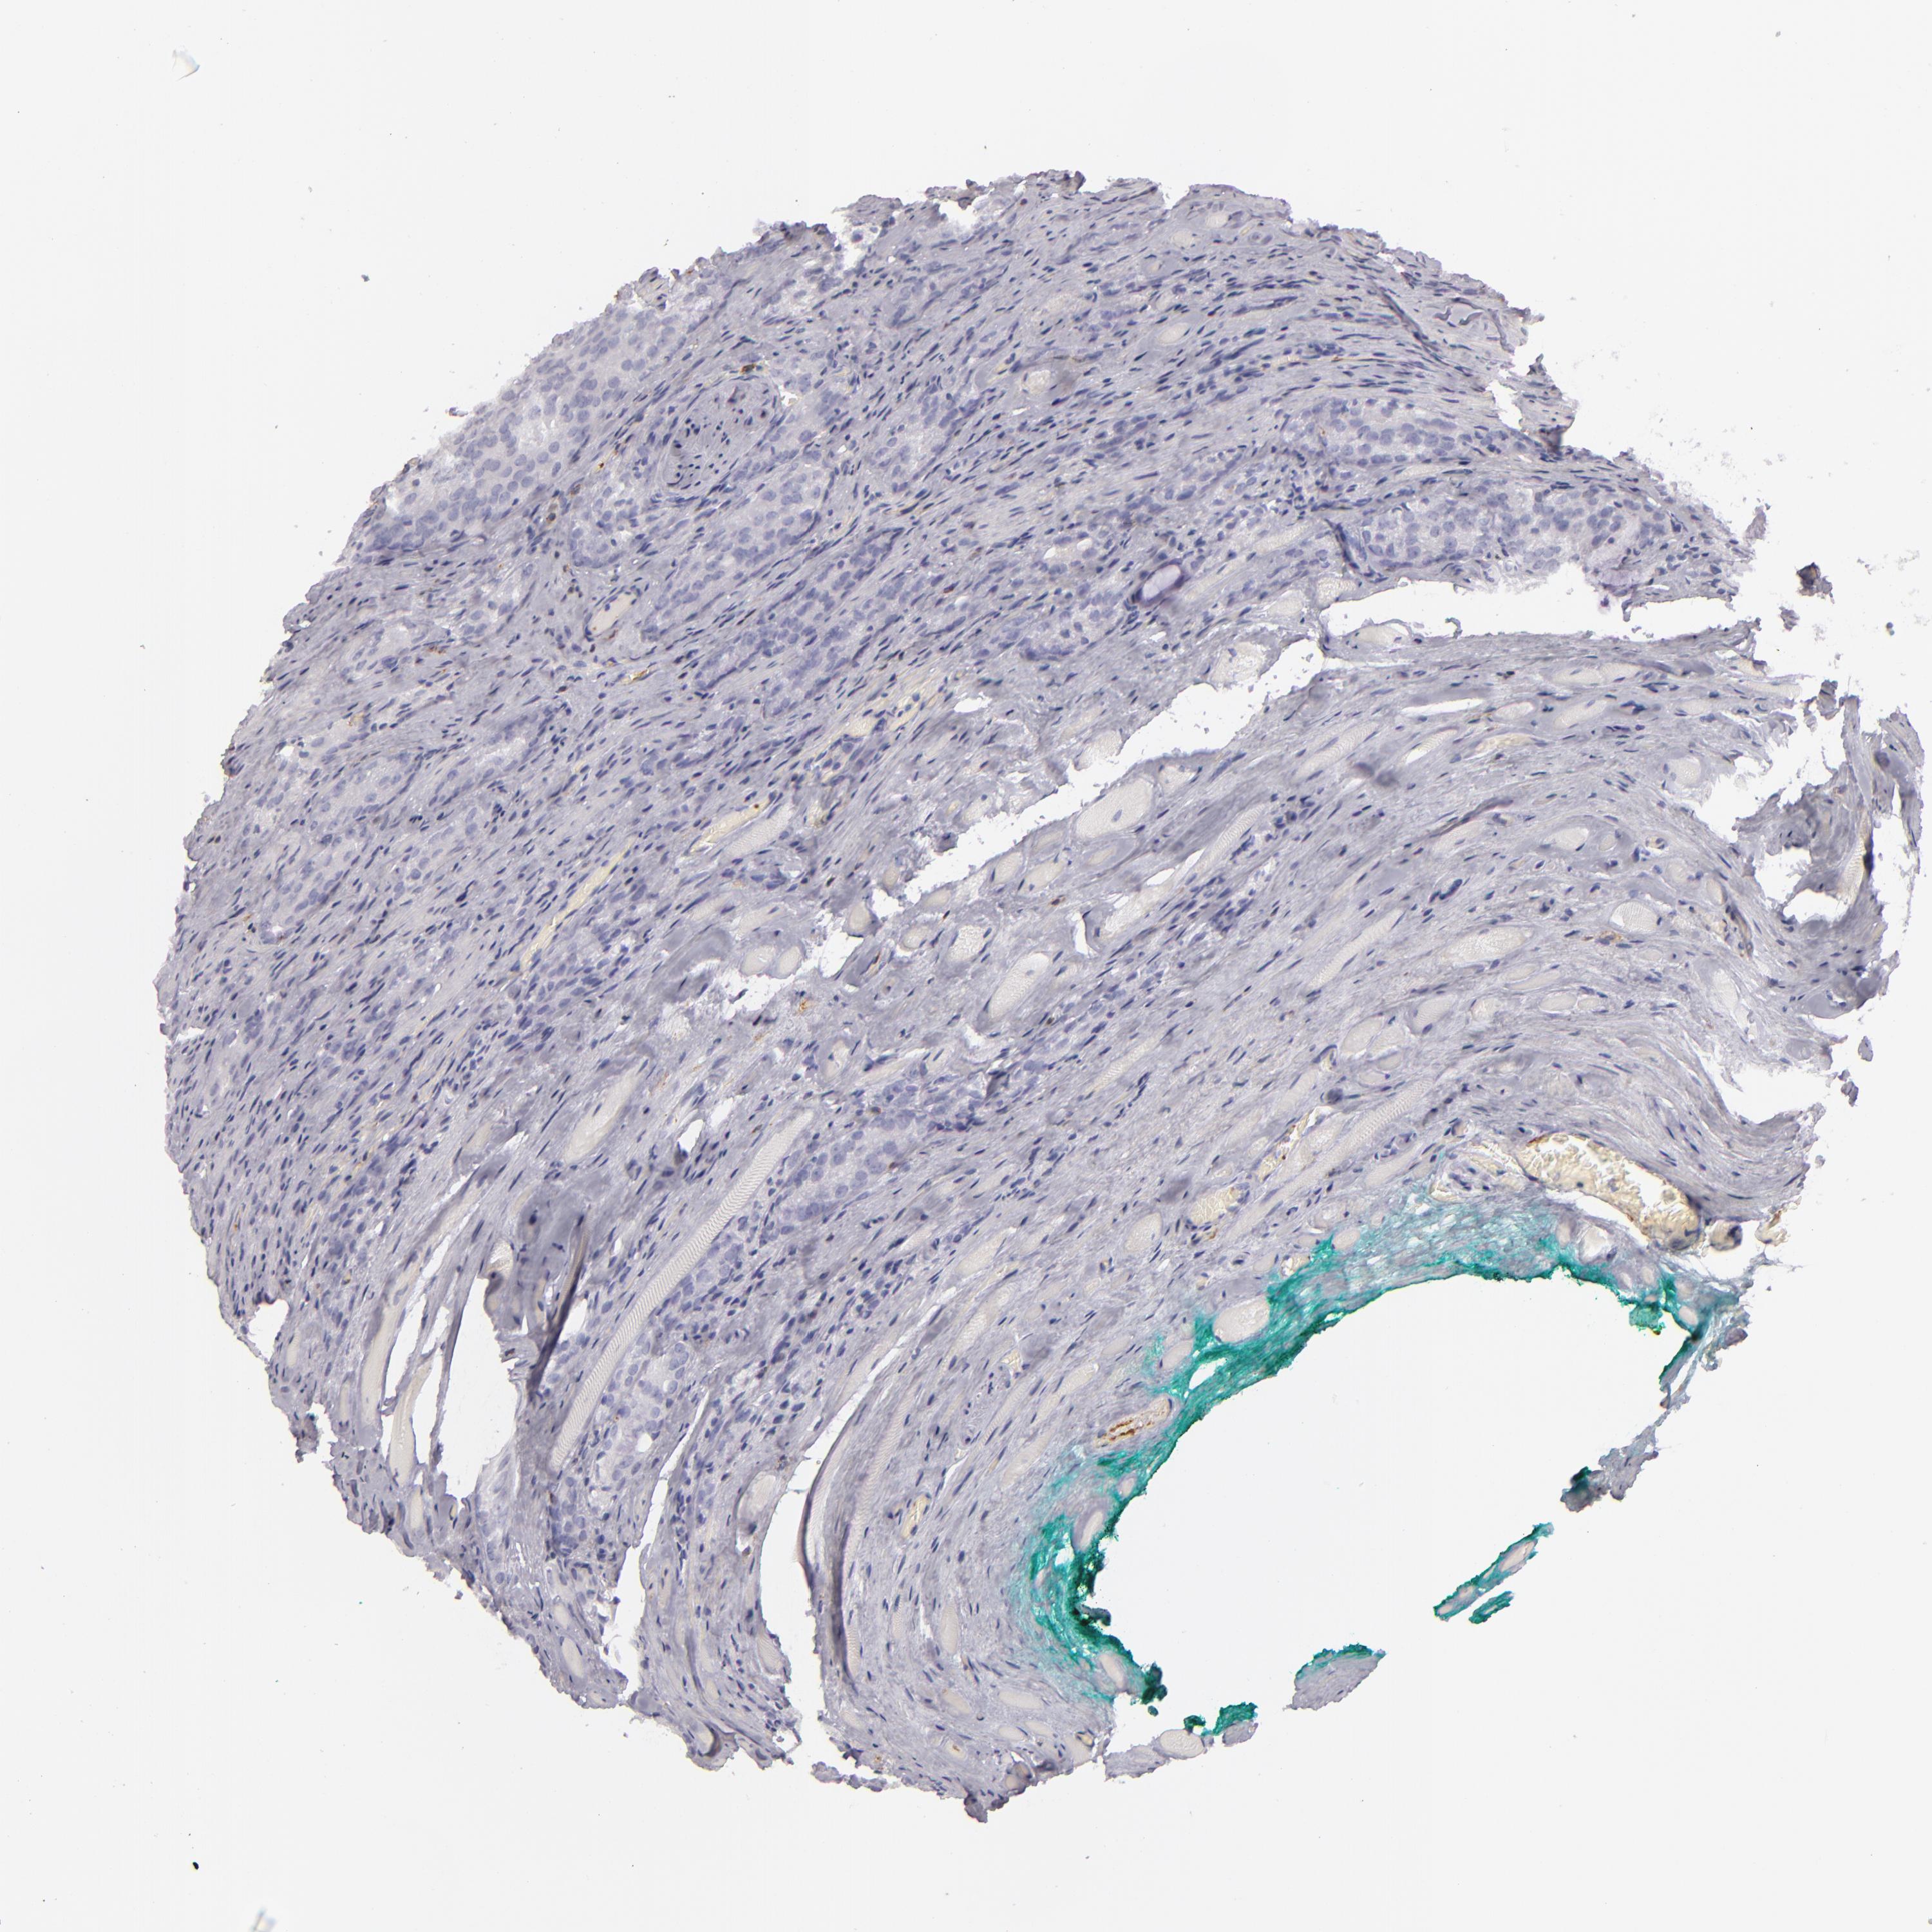

PROSTATE CANCER - Protein expressioni

A mouse-over function shows sample information and annotation data. Click on an image to view it in a full screen mode. Samples can be filtered based on level of antibody staining by selecting one or several of the following categories: high, medium, low and not detected. The assay and annotation is described here.

Note that samples used for immunohistochemistry by the Human Protein Atlas do not correspond to samples in the TCGA dataset.

Antibody stainingi

Antibody staining in the annotated cell types in the current human tissue is reported as not detected, low, medium, or high, based on conventional immunohistochemistry profiling in selected tissues. This score is based on the combination of the staining intensity and fraction of stained cells.

Each image is clickable and will lead to virtual microscopy that enables deeper exploration of all samples and also displays staining intensity scores, fraction scores and subcellular localization as well as patient and tissue information for each sample.

Antibody HPA011157

Antibody CAB002223

Antibody CAB012978

Antibody CAB079960

Staining

High

Medium

Low

Not detected

Intensity

Strong

Moderate

Weak

Negative

Quantity

>75%

75%-25%

<25%

None

Location

Nuclear

Cytoplasmic/membranous

Cytoplasmic/membranous,nuclear

Adenocarcinoma, Low grade

Adenocarcinoma, High grade

Adenocarcinoma, Medium grade

Adenocarcinoma, NOS